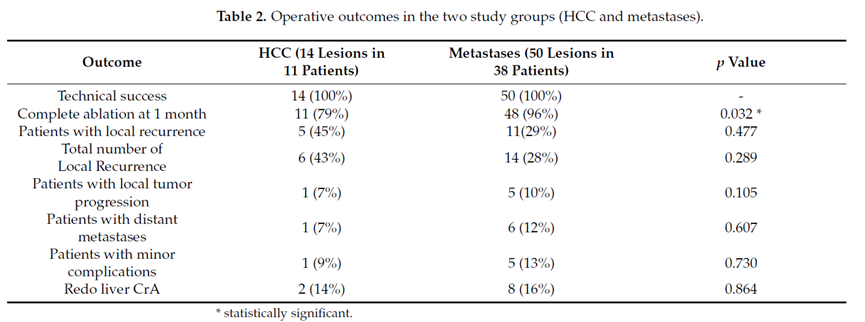

回顾性纳入2015 年至 2020 年期间49 名患者,23 名男性和 26 名女性。平均年龄为 67.5 岁(范围 44-85 岁)。平均随访时间为 19.8 个月(范围 1-60 个月)。对 54 个肿瘤病灶进行了 64 次 冷冻消融 手术(50 个转移癌和 14 个 HCC)。平均肿瘤直径为 2.15 cm(范围 0.5-5 cm)。肝脏转移灶来自结直肠 (n = 23)、乳腺 (n = 12)、胰腺 (n = 7)、肺 (n = 3)、甲状腺 (n = 2)、胃 (n = 1)、卵巢 (n = 1) 和宫颈癌 (n = 2)。

技术成功100%,92% 的病灶中观察到肿瘤完全消融。16 名患者 (33%) 出现局部复发。10 名患者 (20%) 因局部复发或肿瘤消融不完全而接受二次冷冻消融术。

7名患者出现轻微并发症,未发现脓肿形成、胆漏、胆汁瘤或血液学变化。冷冻消融可安全、有效治疗毗邻重要脏器的原发性肝脏肿瘤和肝转移瘤患者,有效控制肿瘤局部进展,使患者生存获益。我国作为肝癌大国,对于肝癌的治疗一直给予高度重视。基于专家共识和相关文献研究结果显示,冷冻消融技术具有高效、低成本、创伤小、适应证广、并发症相对较少等优点,可有效延长患者生存期、提高生活质量、降低患者经济负担。因此,冷冻消融技术在肝癌的应用中有着极高的潜力和广泛的发展空间。